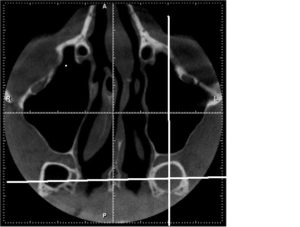

- информативнее других методов обнаруживают сфеноидит компьютерная или магнитно-резонансная томография;

КТ — исследование пазухи с помощью рентгеновского излучения. КТ позволяет выявить аномалии синуса, степень поражения слизистой. При исследовании с помощью КТ определяется уровень гноя в пазухе.

Единственными методами, которые наверняка могут определить сфеноидит, являются компьютерная томография (КТ) или магнитно-резонансная томография (МРТ) –